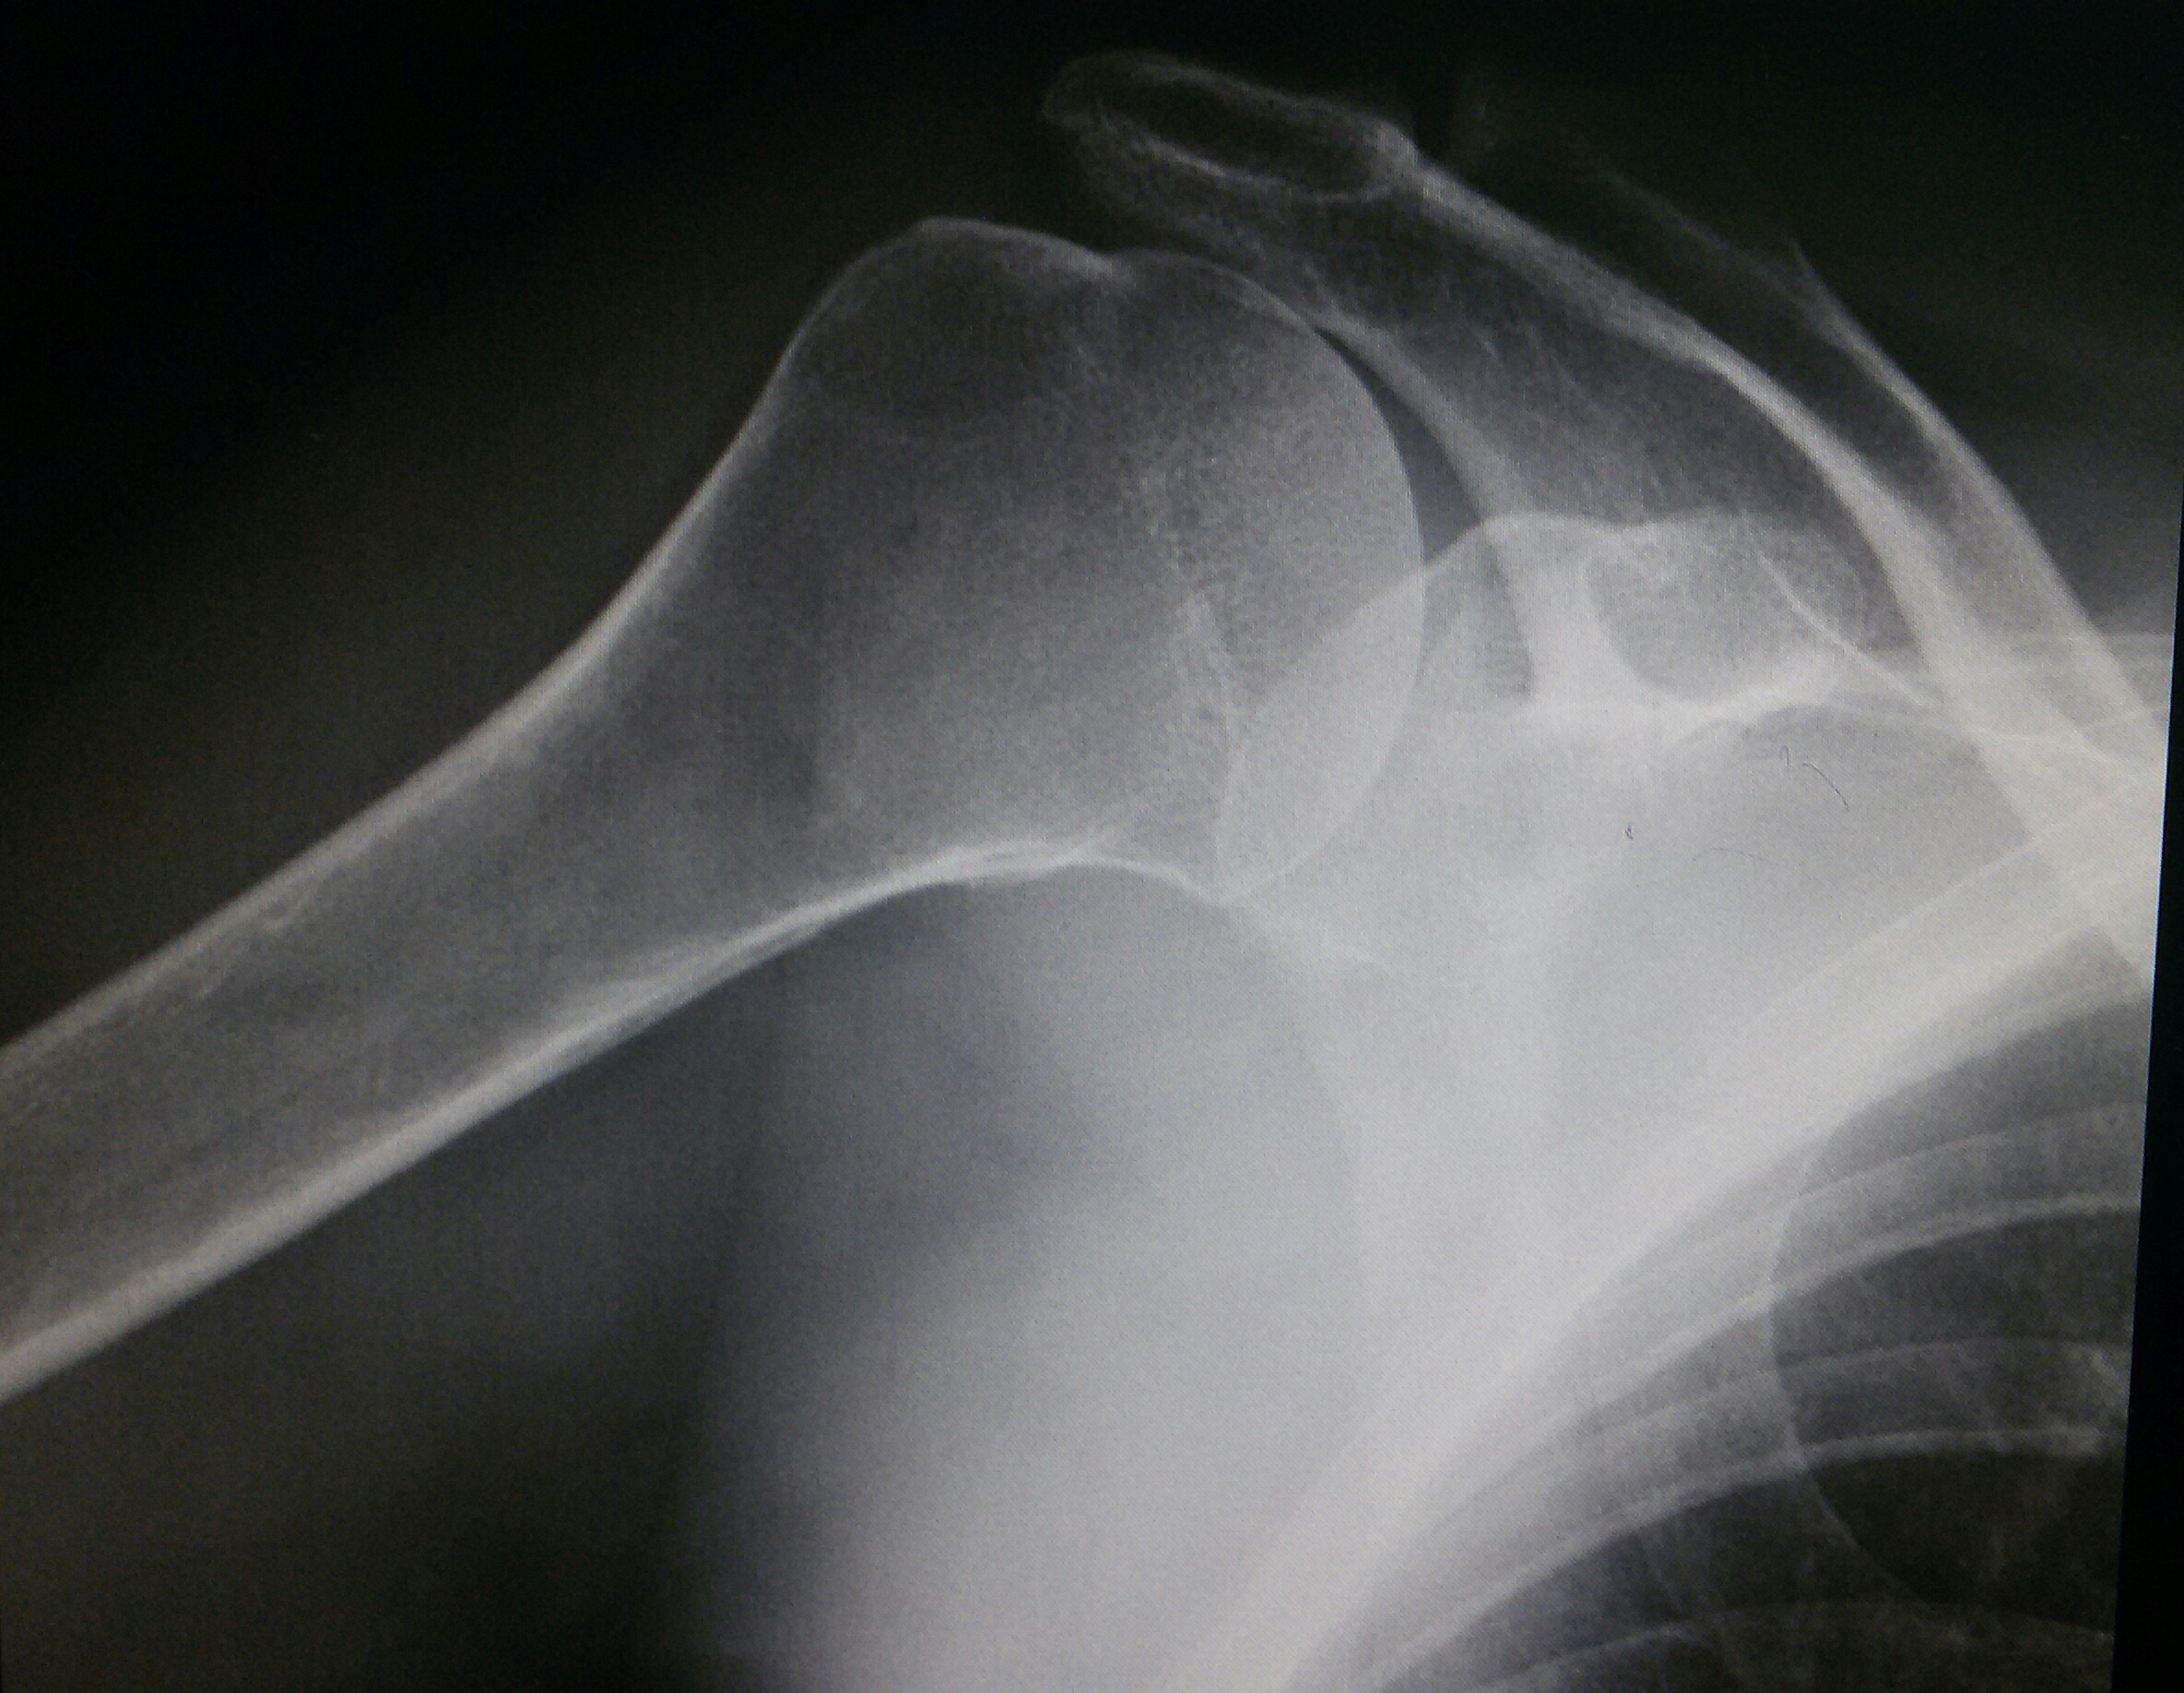

Рентгеновские снимки саркомы плечевого сустава